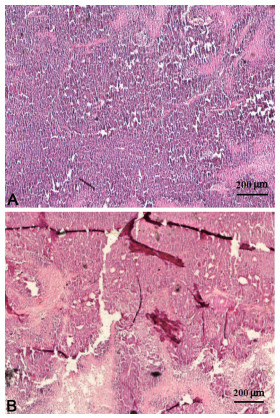

目的 探讨益胃扶正汤对气虚血瘀型胃癌前病变(precancerous lesions of gastric cancer,PLGC)患者的疗效及其对胃黏膜组织蛋白激酶B/雷帕霉素靶蛋白(AKT/mTOR)通路表达的影响。 方法 选取2017年3月—2018年10月在温州市中医院接受治疗的气虚血瘀型PLGC患者88例,根据随机数字表法将患者分为研究组和对照组,各44例。对照组患者给予胃复春片进行治疗,研究组患者在服用胃复春片的基础上给予益胃扶正汤进行治疗。比较2组患者的临床疗效、病理评分、临床症状积分以及不良反应,采用电化学发光免疫分析法检测血清肿瘤标志物水平,采用免疫组织化学法观察胃黏膜组织中p-AKT和p-mTOR在治疗前后的表达。 结果 治疗后,研究组的临床总有效率(86.36%)高于对照组(68.18%,P < 0.05)。2组患者的黏膜炎症、炎症活动度、腺体萎缩、肠上皮化生和异型增生等病理评分均明显降低,且研究组的各项病理评分均低于对照组(均P < 0.05)。2组患者的胃脘胀满、胃痛、倦怠乏力、纳差、大便稀溏、嗳气反酸等症状积分治疗后均明显降低,且研究组的各项病理评分均低于对照组(均P < 0.05)。治疗后,研究组的血清CEA、CA19-9、CA125水平均低于对照组(均P < 0.05)。治疗后,研究组患者胃黏膜组织p-AKT、p-mTOR阳性表达率均低于对照组(均P < 0.05)。2组患者均未出现明显的不良反应。 结论 益胃扶正汤可通过调节AKT/mTOR通路来治疗气虚血瘀型PLGC。 Abstract:Objective To investigate the effect of Yiwei Fuzheng Decoction on qi deficiency and blood stasis precancerous lesion (PLGC) and its effect on the expression of gastric mucosal histone kinase B/rapamycin target protein (AKT/mTOR) pathway. Methods There were 88 patients with qi-deficiency and blood stasis type PLGC who were treated in our hospital from March 2017 to October 2018. The patients were divided into study group and control group according to the random number table method, and 44 cases in each group. Patients in the control group were treated with Weifuchun tablets. Patients in the study group were treated with Yiwei Fuzheng Decoction. The clinical efficacy, pathological score, clinical symptom score and adverse reactions of the two groups were compared. Serum tumor markers were detected by electrochemical chemilescence immunoassay, and the expressions of p-AKT and p-mTOR in gastric mucosal tissues before and after treatment were observed by immunohistochemistry. Results After treatment, the total effective rate of the study group (86.36%) was higher than that of the control group (68.18%, P < 0.05). Mucosal inflammation, inflammatory activity, gland atrophy, intestinal metaplasia, dysplasia and other pathological scores in the two groups were significantly reduced, and the pathological scores in the study group were lower than those in the control group (all P < 0.05). The symptom scores of patients in the two groups were significantly reduced after treatment, including full distension, stomachache, fatigue, poor appetite, loose stools in stool, and belching regurgitation, etc., and the pathological scores in the study group were all lower than those in the control group (all P < 0.05). After treatment, the levels of serum CEA, CA19-9 and CA125 in the study group were lower than those in the control group (all P < 0.05). After treatment, the positive expression rates of p-AKT and p-mTOR in gastric mucosa of the study group were lower than those in the control group (all P < 0.05). There was no obvious adverse reaction in both groups. Conclusion Yiwei Fuzheng Decoction may treat qi deficiency and blood stasis type PLGC by regulating AKT/mTOR pathway. -